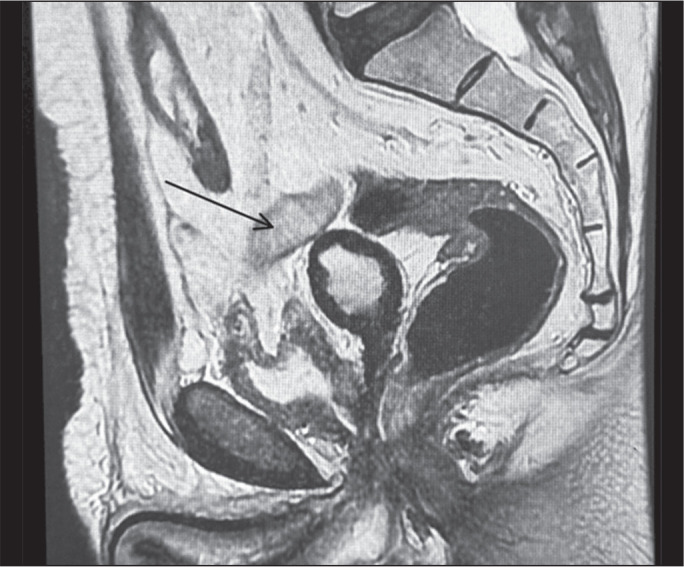

For ultrasound-guided prostate biopsy, a transperineal approach is emerging as a superior alternative to the transrectal approach because the former is associated with a lower risk of infection. This pictorial essay aims to highlight the broader applications of transperineal ultrasound (i.e., those beyond prostate biopsy). We demonstrate various diagnostic and therapeutic uses of transperineal ultrasound, including lymph node biopsies, abscess drainage, hydrogel spacer placement for radiotherapy, and penile biopsies. Details of the transperineal approach, including patient positioning and preparation, are described. In addition, the effectiveness and safety of the method are demonstrated. Our results underscore the versatility of transperineal ultrasound and its potential to enhance clinical practice, demonstrating its importance as a minimally invasive technique with significant clinical benefits in various medical contexts.